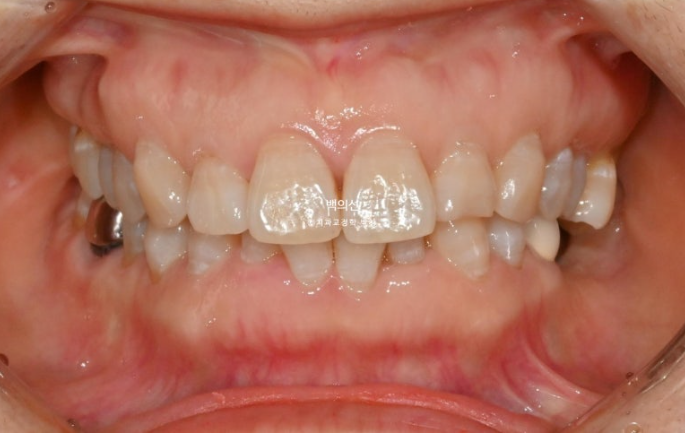

정면에서는 아래 앞니 일부가 윗니에 가려져 안 보일정도의 심한 과개교합을 보입니다.

앞니 두 개가 튀어나와 돌출이며

아래 앞니는 치아가 많이 겹쳐져 있습니다.

특히 가운데 앞니와 옆 앞니는 50% 정도가 겹쳐진 상태